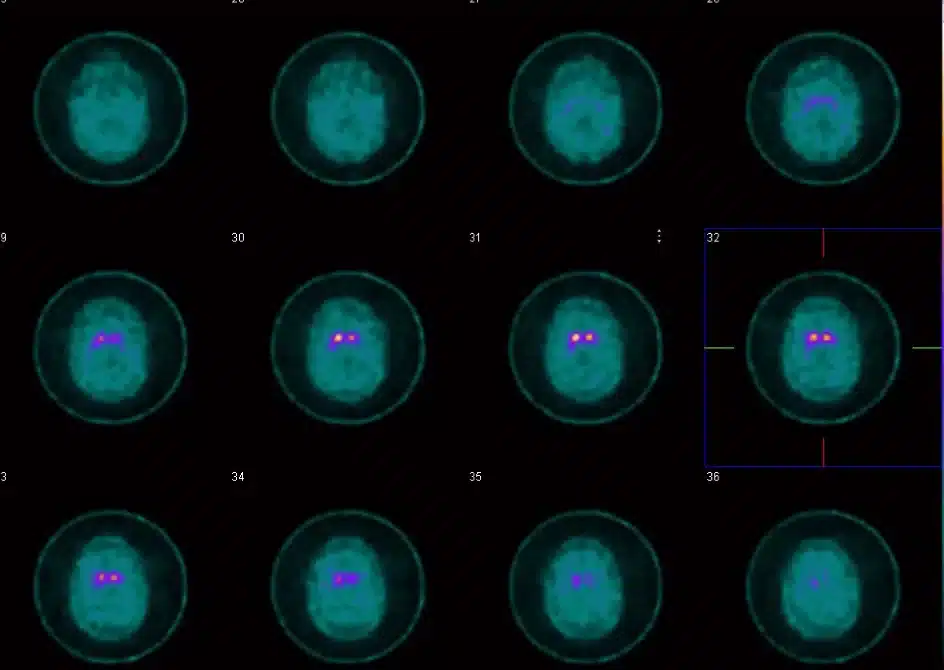

Everything culminated last week when I went to Mount Sinai for an MRI and a DAT Scan (a Dopamine Transmitter Scan, to help confirm Parkinson’s). For the DAT Scan, they injected dye into my blood that attached itself to dopamine so they could see it light up in my brain (Parkinson’s is the progressive loss of dopamine).

We Zoomed with the doctor yesterday, and as she explained, that image in the middle on the right shows the Dopamine receptors in my brain. The one on the left looks like a comma or an eye with a teardrop; the one on the right is missing its teardrop. That’s actually the left side of my brain and it’s missing those Dopamine receptors, hence the rigidity and tremor on my right side.